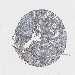

CERVICAL CANCER - Protein expressioni

A mouse-over function shows sample information and annotation data. Click on an image to view it in a full screen mode. Samples can be filtered based on level of antibody staining by selecting one or several of the following categories: high, medium, low and not detected. The assay and annotation is described here.

Note that samples used for immunohistochemistry by the Human Protein Atlas do not correspond to samples in the TCGA dataset.

Antibody stainingi

Antibody staining in the annotated cell types in the current human tissue is reported as not detected, low, medium, or high, based on conventional immunohistochemistry profiling in selected tissues. This score is based on the combination of the staining intensity and fraction of stained cells.

Each image is clickable and will lead to virtual microscopy that enables deeper exploration of all samples and also displays staining intensity scores, fraction scores and subcellular localization as well as patient and tissue information for each sample.

Antibody HPA017283

Staining

High

Medium

Low

Not detected

Intensity

Strong

Moderate

Weak

Negative

Quantity

>75%

75%-25%

<25%

None

Location

Nuclear

Cytoplasmic/membranous

Cytoplasmic/membranous,nuclear

Squamous cell carcinoma, NOS

Adenocarcinoma, NOS